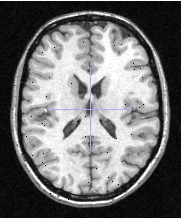

Selection of threshold : a image is composed with grey levels from 0 to 4095 (for example image). The grey level '0' is in fact black color and the '4095' is white color, all others grey levels are between 1 and 4094. To know the minimun and the maximun of grey level, you can put your image in a browser in Anatomist and read tex_min (black) and tex_max (white) attributes. To handle grey levels of your image, use ROI module of Anatomist (option Connectivity Threshold).

Test image, tex_min = 0, tex_max = 4095